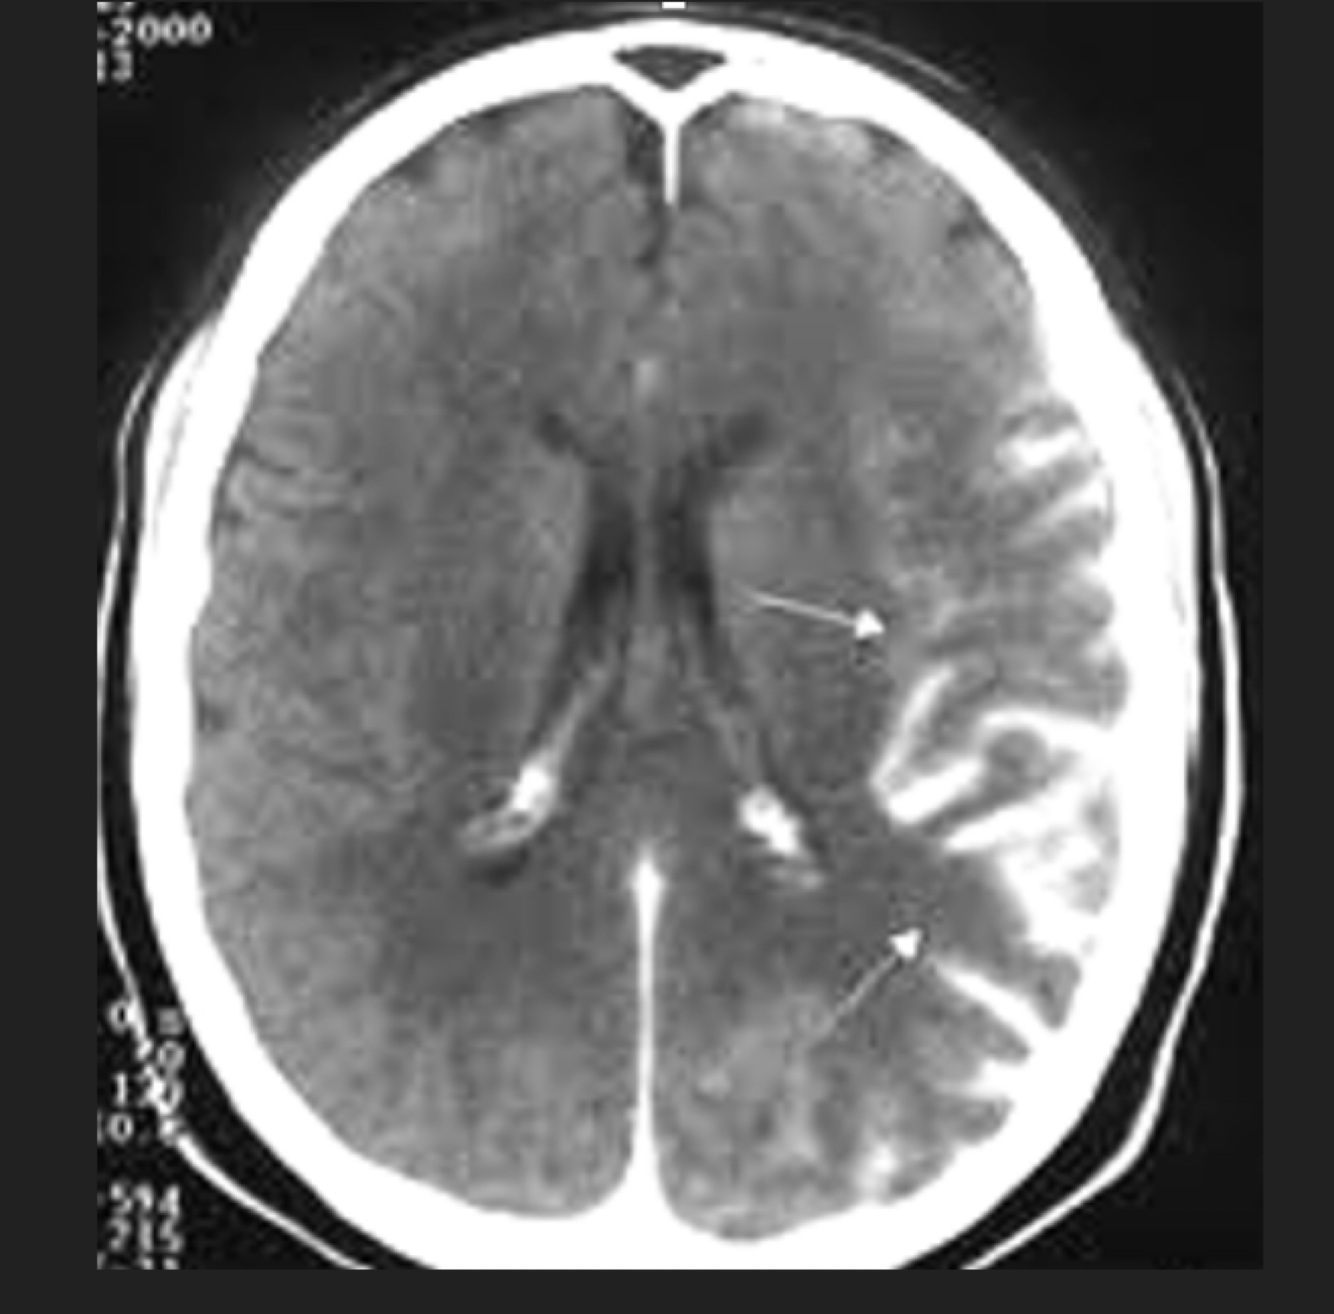

Q

Paciente con accidente automovilístico. Glasgow 5

A

Hemorragia subaracnoidea